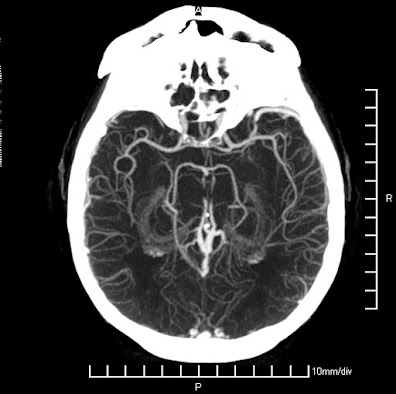

En la medicina moderna, el poder de la imagen es innegable. Las imágenes médicas son una herramienta fundamental y cada vez más sofisticada en el diagnóstico y tratamiento de enfermedades. Desde la radiografía simple hasta la resonancia magnética y la tomografía por emisión de positrones (PET), las imágenes médicas nos permiten ver dentro del cuerpo humano de una manera nunca antes posible.

La tecnología de imagenología sigue avanzando a pasos agigantados. Nuevas técnicas y tecnologías están siendo desarrolladas constantemente, lo que nos permite ver el cuerpo humano con una claridad y detalle cada vez mayores. Desde la tomografía computarizada de doble energía hasta la imagenología molecular, las posibilidades son infinitas.